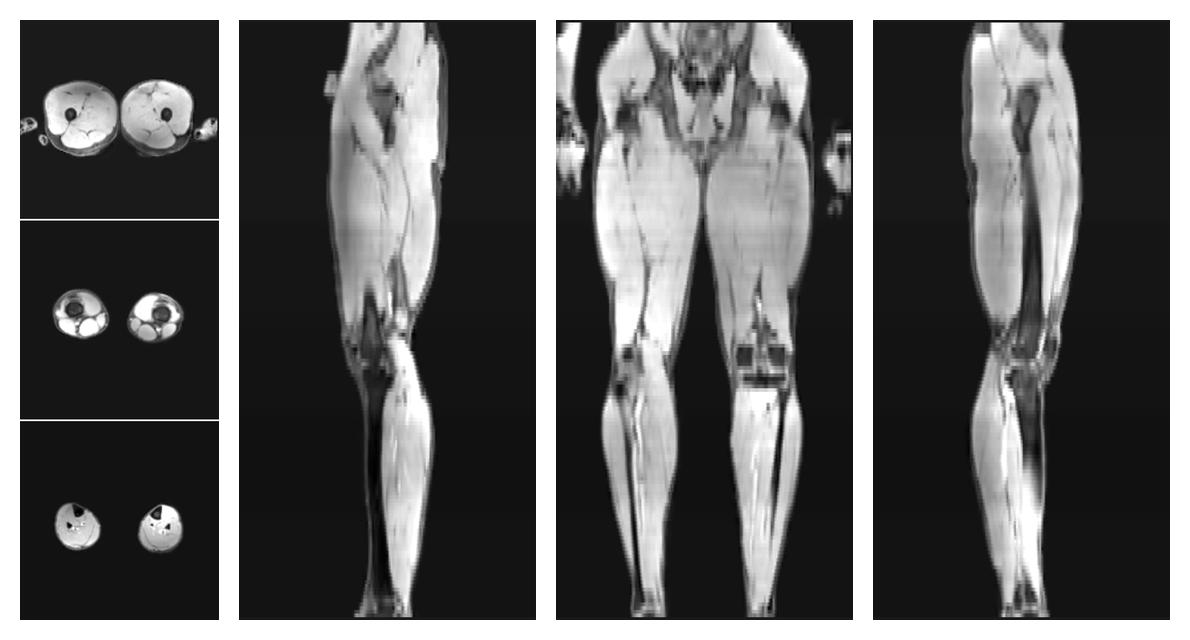

• Mean diffusivity

IVIM corrected whole leg muscle mean diffusivity obtained from diffusion tensor imaging.

• Fractional anisotropy

IVIM corrected whole leg muscle fractional anisotropy obtained from diffusion tensor imaging.